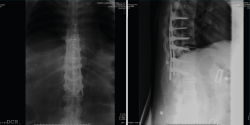

Después de realizar un control radiológico postoperatorio (Figura 6), inició la deambulación con ortesis semirrígida dorsolumbar en el postoperatorio inmediato. Mantuvimos la ortesis durante 2 meses, iniciando la rehabilitación con una evolución clínica excelente.

Figura 7. Control a los 2 meses de la cirugía.

Se realizó un control a los 2 meses de la cirugía, previo al inicio de rehabilitación (Figura 7).